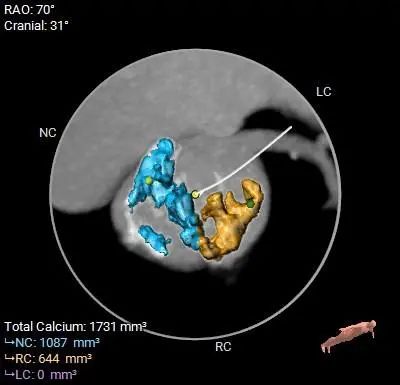

Type 0型二叶式主动脉瓣,左右冠脉同窦,重度钙化,左(右)冠窦和无冠窦内钙化弥漫分布于窦内,瓣叶对合缘存在局部钙化粘连及纤维增厚

HU850